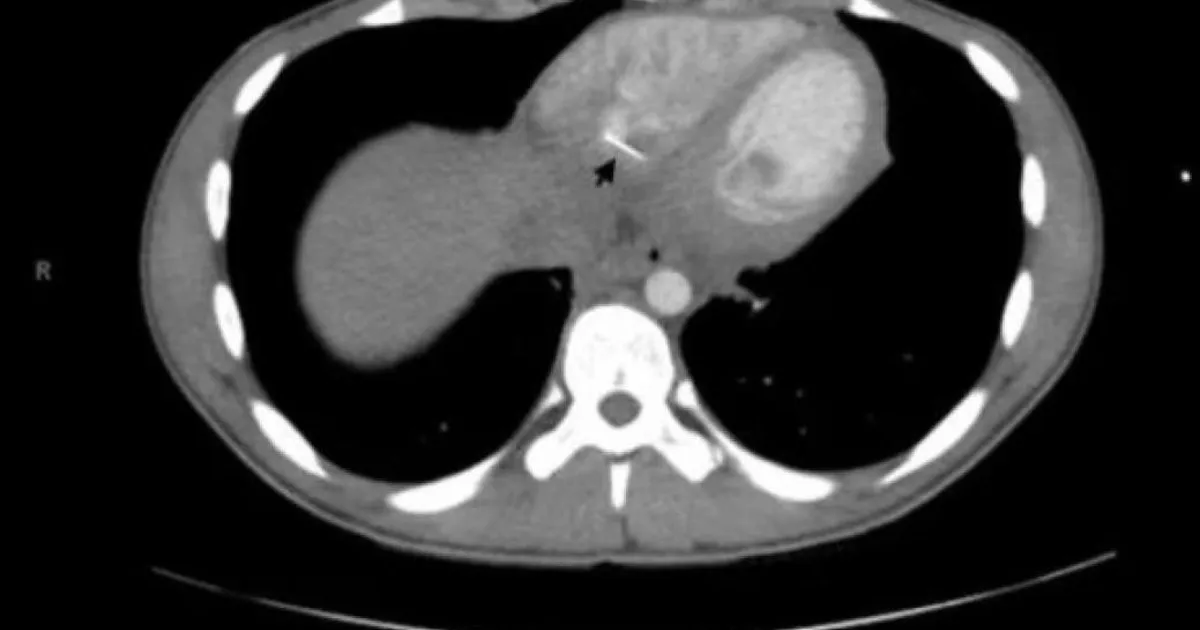

PulpStati Uniti, 17enne ricoverato con forti dolori al petto: senza precedenti, un ago da cucito conficcato dritto nel cuore5 settembre 2020